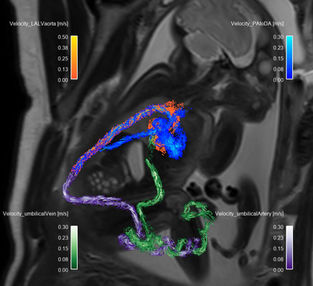

Physiological Fetal Cardiac Anatomy

Pathological Fetal CHD